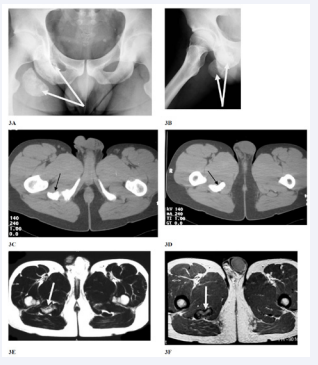

Pelvic heterotopic ossification may be present in young active patients and usually results to muscular injuries that lead to intramuscular hematoma formation. This hematoma may lead to ectopic bone mass formation which according to its size and location may irritate the sciatic nerve. We already have published an analogue case and our findings were similar to those reported by Lopez et al some years later [34,35]. The formation of heterotopic bony mass usually follows injuries near to the tendon bone insertion site. In both cases the ectopic bone was close to the sciatic tuberosity (Figure 3),

Figure 3: Anteroposterior (3A) pelvic and lateral (3B) right hip x-rays Two circumferential bony masses are pointed by white arrows. CT scan images (3C and 3D) where the ectopic bone is pointed by black arrows. MRI images (3E and 3F) where the pathology is pointed by white arrows.

where the muscles of the flexor compartment of the thigh mostly originate. In our case symptoms where increased while the patient was sitting. In both cases the size of the ectopic bony tissue was considerable, able to affect the ischiofemoral space, causing a ‘kind’ of deep gluteal syndrome (DGS), as described above. After the ectopic bone removal the patients recovered fully, without signs of recurrence in at least 2 years follow up period. In both cases the symptoms of the affected hip were mild and could have been under-estimated. Electromyography findings may be helpful as long as were indicative in our case (deep peroneal nerve dysfunction with pathological measurement of f-wave latency). Lopez et al, in order to differentiate diagnosis performed a selective L4-L5 foraminal nerve root block, which was negative [35]. So, in similar cases at least an antero-posterior pelvic x-ray should always be thoroughly reviewed.